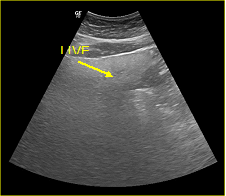

In a 4-years period (from 2016 to 2019) a retrospective study of 887 patients with fatty infiltration of the liver was performed, out of which 608 were males and 272 were females, aged 42 to 69 and 7 obese children (age from 8 to 13 years). All patients were examined in the ultrasound cabinet of our hospital (hospitalized, regular appointments and emergency incidents) and subjected to upper abdominal ultrasound scan, with convex transducer 4C MHz, in three ultrasound imaging planes: transverse, oblique and sagittal planes.5−7 In order to better depict the liver, especially in obese patients or those with excessive intestinal gas, the patients were asked to inhale deeply and hold their breath for the duration of the ultrasonographic examination for a few seconds at a time, so that the liver could be visible in its entirety. The ultrasound examination revealed the echogenicity of the parenchyma of the liver and was compared with the parenchyma of the right kidney, the spleen and the pancreas (Figure 1−3). Τhere is always the risk of missing a diagnosis of mild hepatic steatosis on ultrasound if there is concurrent chronic renal disease, which increases the echogenicity of the kidneys (Figure 4), if there is any doubt that the patient might have a chronic renal disease, comparison of the liver to the left kidney and the spleen may be useful.8

Figure 1 Right renal cortex appearing hypoechoic compared to the liver parenchyma.

The fatty infiltration of the liver is shown on ultrasound with significantly increased echogenicity "bright liver", in comparison with the right kidney cortex (Figure 1). Normally, the liver and the renal cortex have similar echogenicity, relative to the parenchyma of the pancreas and the spleen. The maximum diameter of the liver in the midclavicular line (MCL) was increased, right lobe>15 cm (Figure 5). Also significant features are the absence of mass effect on intrahepatic vasculature (Figure 6) as well as the poor visualization of the deep parts of the liver (Figure 7), due to decreased permeability of the acoustic beam. A focal or diffuse morphology has been shown to increase the echogenicity of the fatty liver. Differential diagnosis is caused by focal fat infiltration (Figure 8), which has a geographic distribution. In this case, hypoechoic areas correspond to normal hepatic parenchyma on fatty infiltration sites, whereas, normal parenchyma islets can easily be identified due to their typical positions, in front of the right branch of the portal vein, its division, around the area of the gallbladder and the caudate lobe.9−13